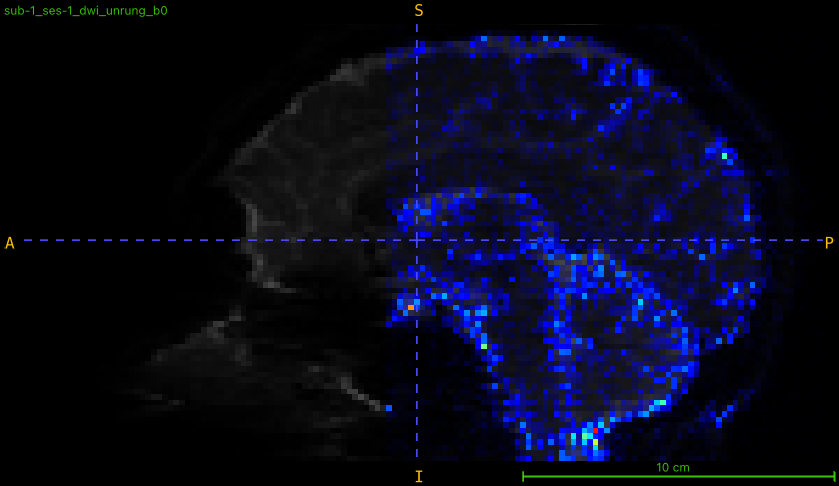

And one using the Q4 sampling scheme (same site but prior to a gradient coil replacement):